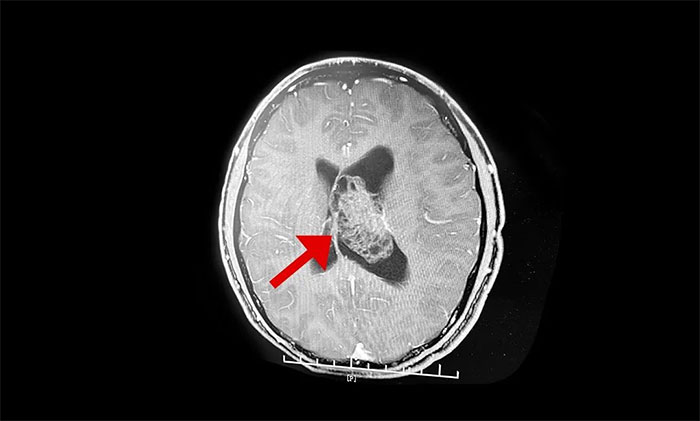

最終被診斷為中樞神經細胞瘤。中樞神經細胞瘤屬於比較罕見的腦腫瘤,一般直徑超過三公分即為巨大腫瘤,而李威腦室內的腫瘤直徑竟達七公分,接近一個拳頭大小。幸運的是,順利手術切除。

▲ 非典型性中樞神經細胞瘤